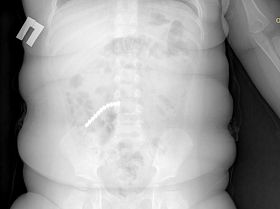

Главная проблема детской кардиологии — пороки сердца

Врач ДРКБ рассказала болезнях детей в Бурятии